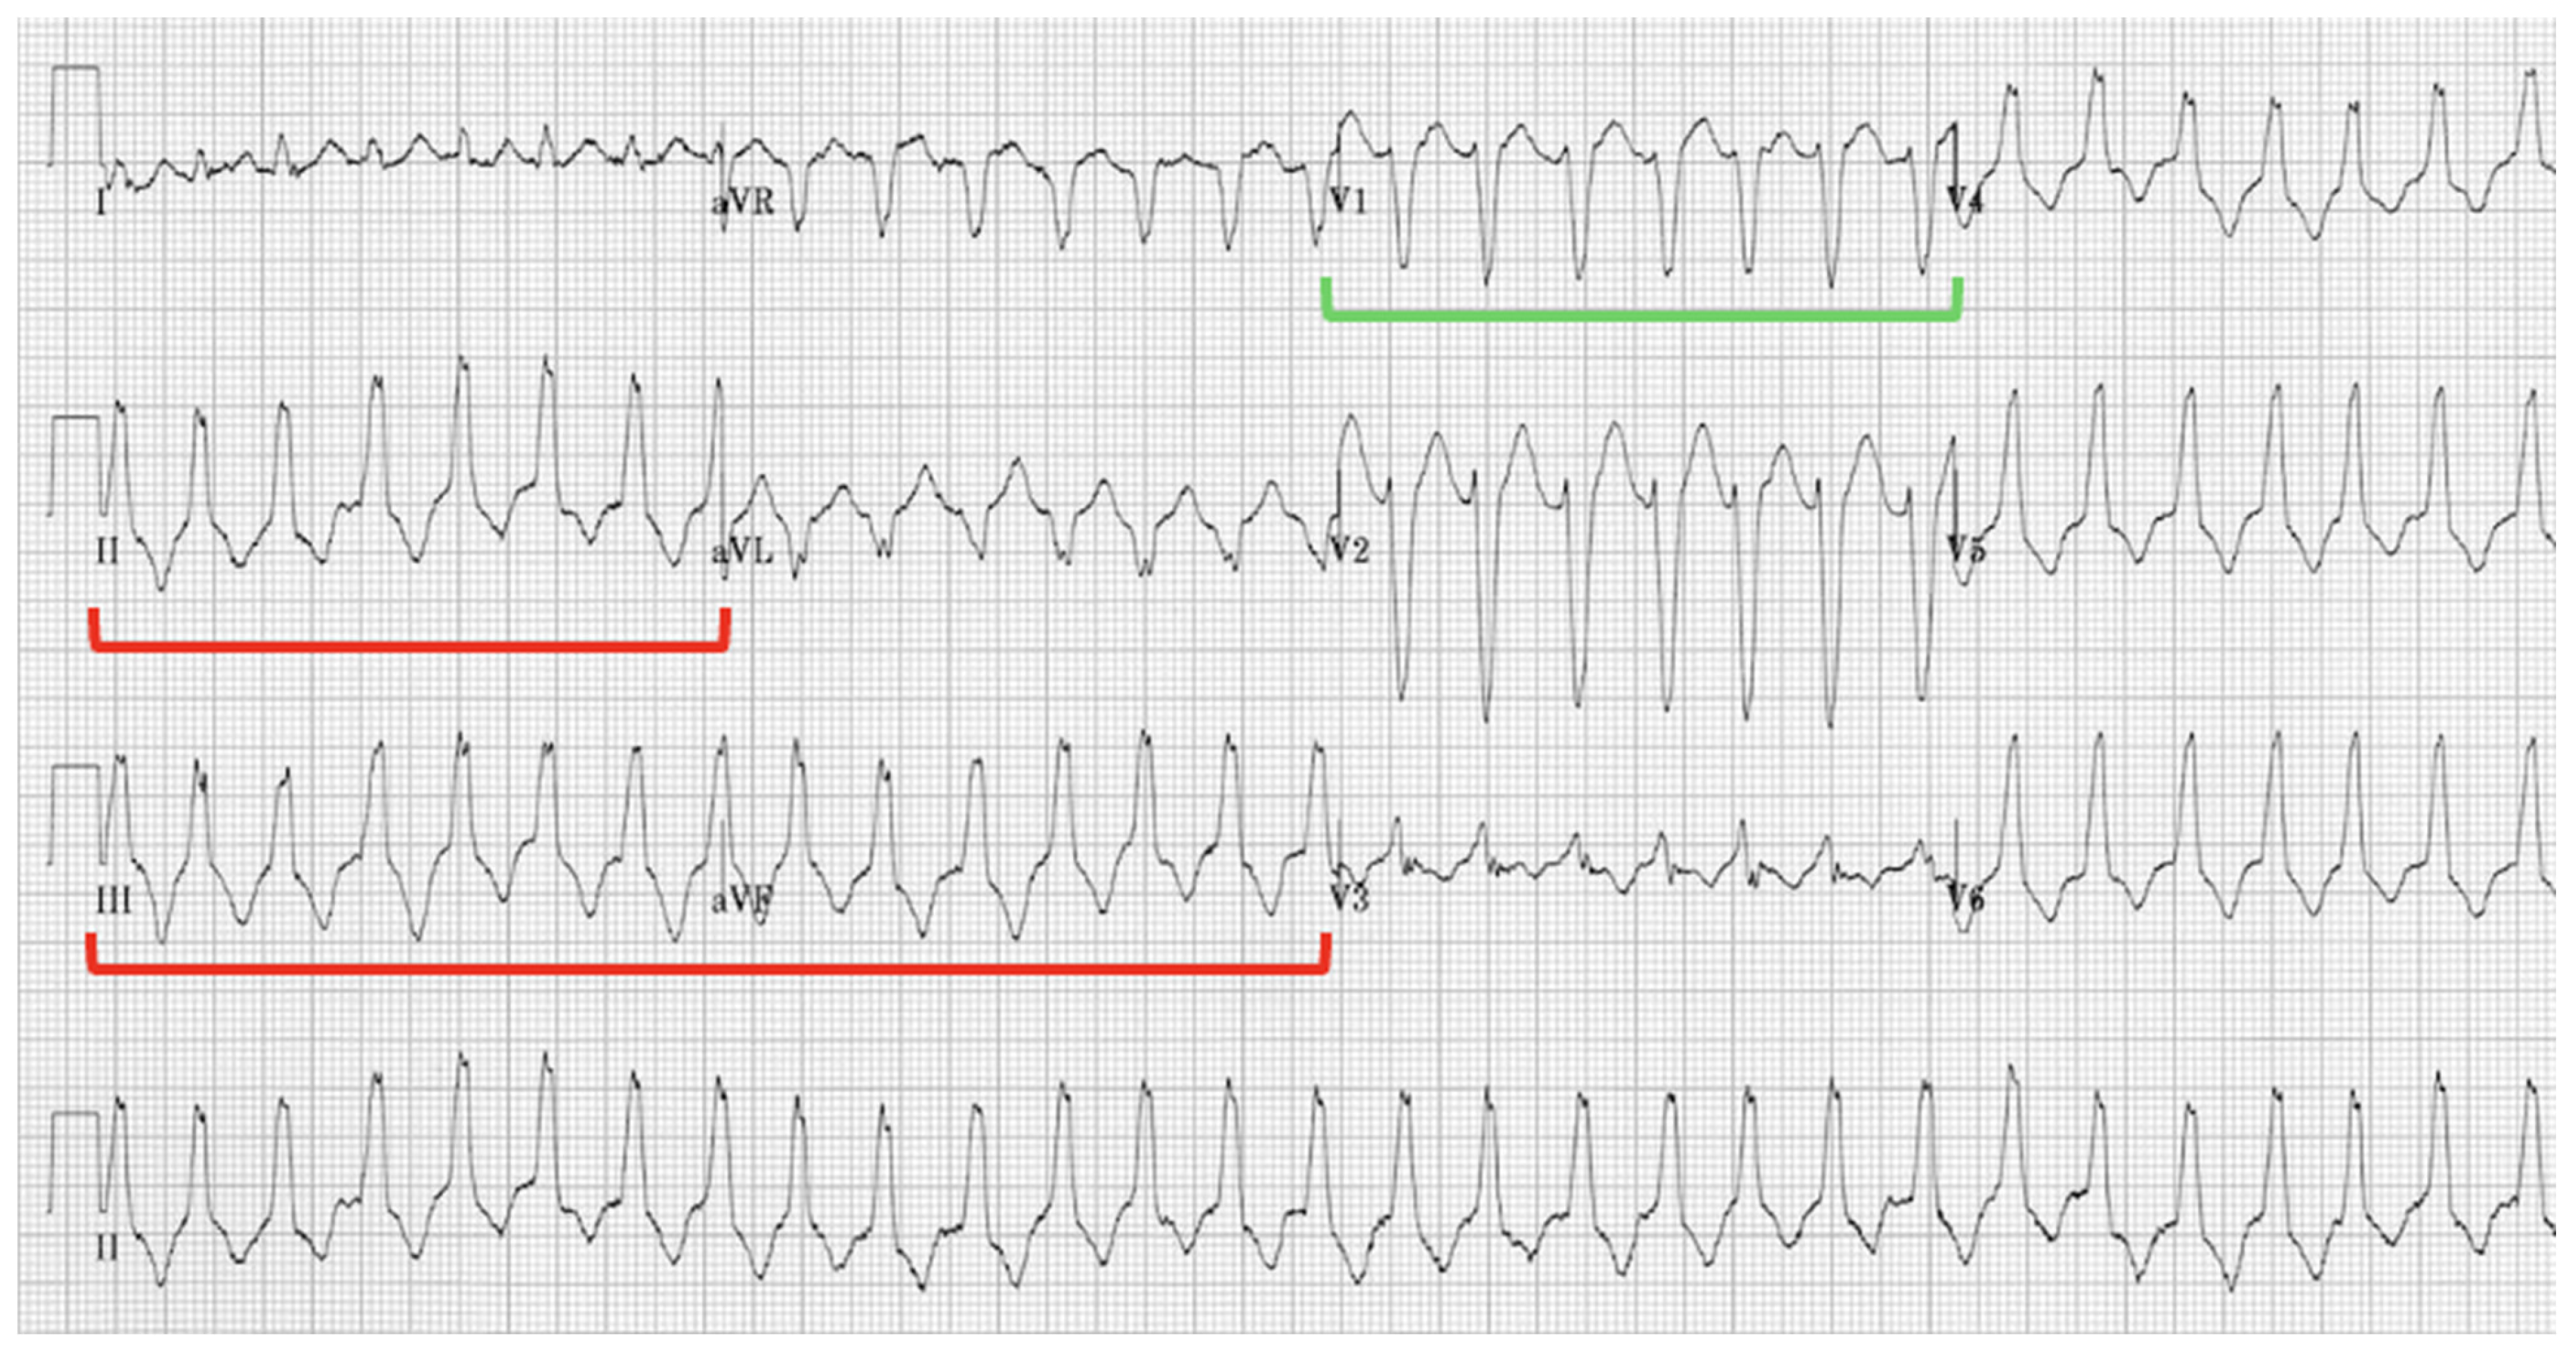

5.2.1. EKG and Holter Monitoring